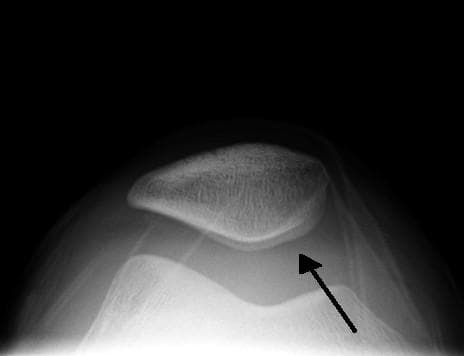

vignette|Imagine radio d'une hydarthrose L’hydarthrose est l'accumulation anormale de synovie dans l'articulation par augmentation de sa sécrétion. La pression intra-articulaire est alors augmentée, entraînant des douleurs lors de sa sollicitation. Elle est souvent localisée au genou (présence du signe du glaçon) et peut évoluer en kyste poplité.